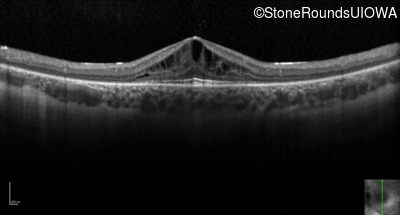

Optical Coherence Tomography - Left - 20/32 -2

Exemplar / OCT Stack